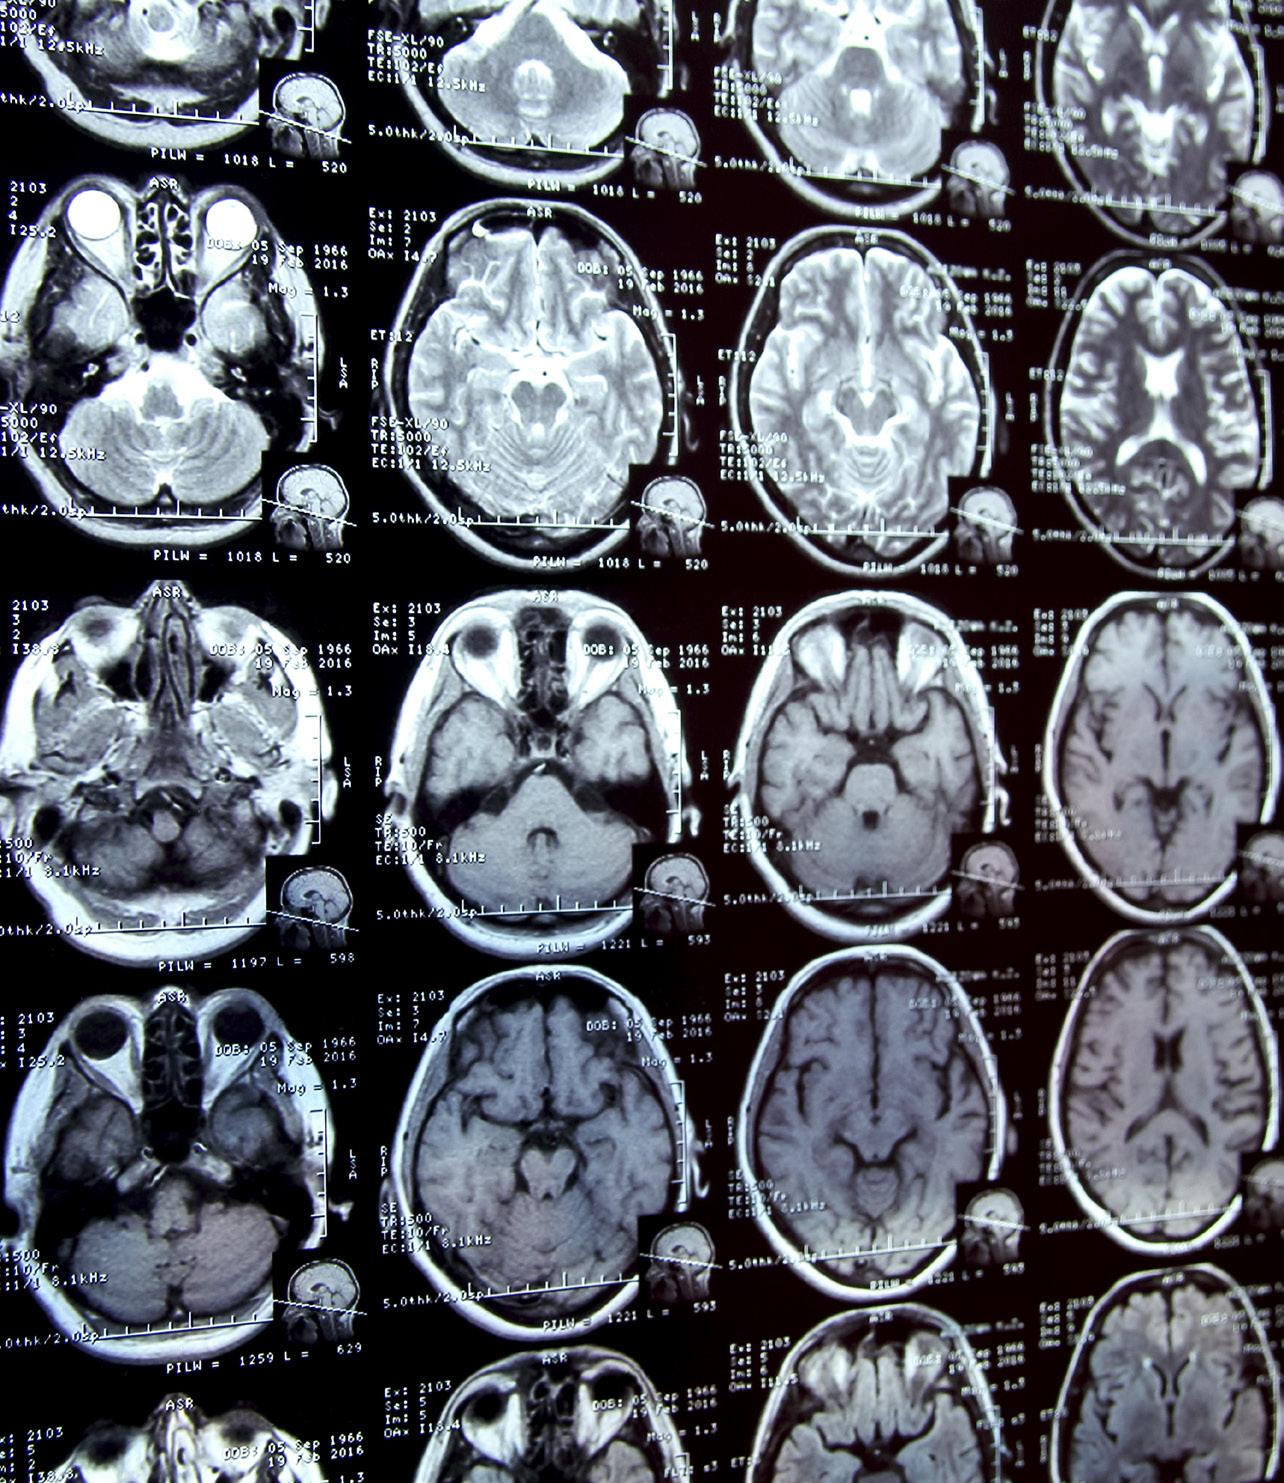

• Interpreted CT, MRI, radiography, and ultrasound images of abdomen and pelvis

• Performed advanced imaging examinations including contrast enhanced ultrasound (CEUS)

Diagnostic and Interventional Neuroradiology

Full-Time Faculty Complement: 11

• Interpreted all adult and pediatric neuroimaging (CT, MRI); performed image-guided vascular and non-vascular procedures of brain, head and neck, and spine